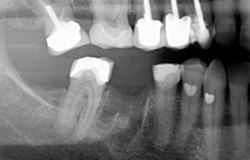

A bridge is one of the options to replace one or more missing teeth. It is a permanent fixture which is anchored to the adjacent natural tooth or teeth (the abutment) to 'bridge' the gap where the tooth (or teeth) is missing (the pontic). This also prevents the adjacent natural teeth from drifting. A bridge is a great option if you do not wish to have dental implants or a denture to replace your missing tooth or teeth. There are many different designs and materials which can be used for bridges: your dentist will discuss the best option for you. Each bridge is individually handcrafted by our dental technician to create a healthy, natural look which also sits comfortably with your bite.

Cantilever Bridge – This is a bridge with one false tooth or 'pontic' which is attached to one crown 'the abutment' Fixed- Fixed Bridge – Generally consists of three crowns joined together, one at each end which cover your natural teeth and a crown in the middle which replaces your missing tooth.- Some bridges may actually be four, five or even more crowns joined together, designed to replace more than one of your missing teeth Adhesive Bridge – This bridge has a false tooth (the pontic) to which a metal or tooth coloured 'wing' is attached to a natural tooth on either side of the missing tooth. This type of bridge can have one or two wings Dental bridges can be made using the following materials – all metal (often gold) or tooth coloured bridges such as porcelain fused to metal (often gold or a gold alloy), full ceramic (porcelain) or composite (plastic with glass particles embedded). The material used will depend on why you are having the bridge. Two appointments are necessary, the first to prepare the tooth for the bridge abutments and the second to fit your bridge.